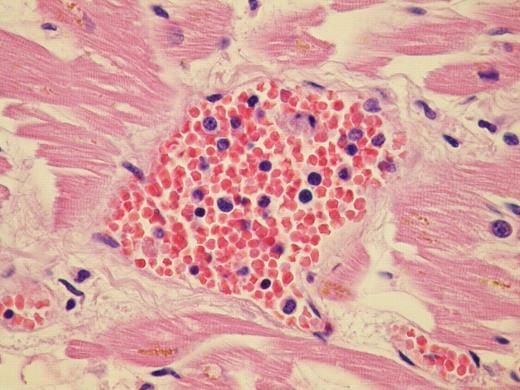

We report the case of a 60 year old patient with advanced Post Thrombocitemia Myelofibrosis extensively localized in almost all organs. He was referred to our Center in April 2008; clinical, radiological and haematological features suggested an evolution into Myelofibrosis. Molecular analysis for V617F JAK2 mutation was negative. Hemogram showed leukocytosis, mild anemia and normal platelet count. After few months of treatment with Danazol and Thioguanine, he was admitted for hemodynamic failure; echocardiography and chest X-ray were normal; abdomen CT scan confirmed important splenomegaly and didn't show any deep thrombosis. During hospitalization he developed massive intracerebral haemorrhage, cause of death. Post mortem histopatological examination documented osteomyelosclerosis and wide localization of extramedullary hematopoiesis. Morphological examination of the specimens showed an extensive dissemination of megakaryocytes, erythroid and myeloid precursors immunoreactive with factorVIII, hemoglobin, and myeloperoxidase respectively. We documented intravascular involvement of spleen, liver, lymph nodes, lungs, adrenal glands, myocardium, and central nervous system. Noteworthy fibrosis associated with haematopoietic cells were broadly distributed into retroperitoneal tissue.